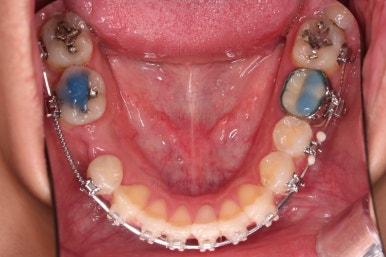

초진 시 입안의 모습입니다.

화살표는 결손 부위, 동그라기믄 유치잔존과 매복치아 부위입니다.

장치를 부착한 모습입니다.

이번 환자분은 자가결찰 세라믹(엠파워 클리어) 장치를 선택하셨고요.

잔존유치는 발치했고, 앞니 가짜치아는 벗겨내고 새로운 가짜치아를 와이어에 묶어주었습니다.